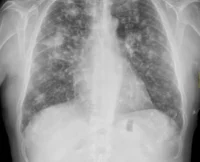

Hipertensión pulmonar

La hipertensión pulmonar es una condición grave caracterizada por un aumento anormal de la presión en las arterias pulmonares, los...